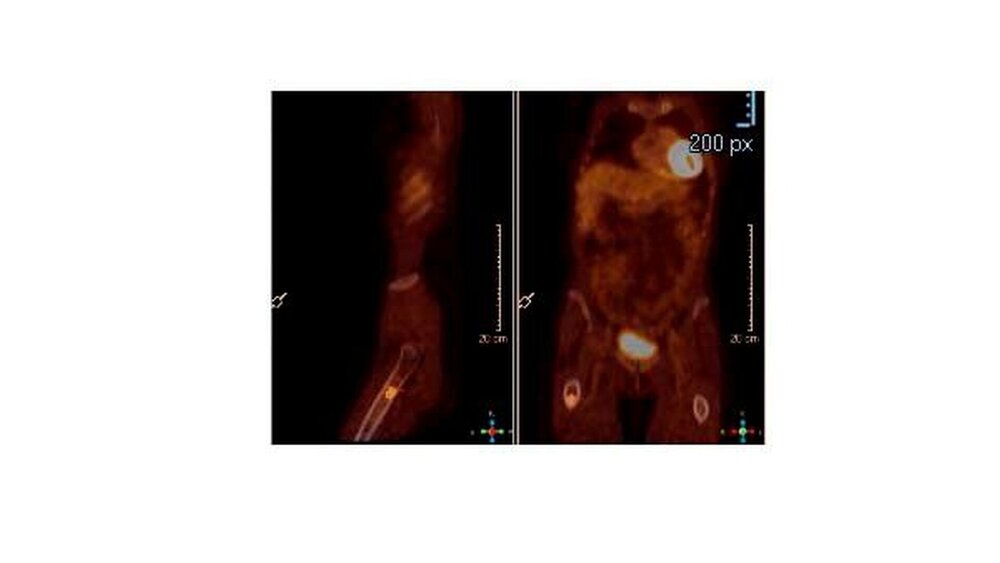

Patientin mit Knochenmetastasen

Um das weitere Wachstum und die Zerstörung im Knochen zu stoppen, waren neben der Tumortherapie die Behandlung mit hemmenden Zytostatika nötig. Das gelang ausgezeichnet, denn die ersten PET-CT Bilder stammen aus dem Jahr 2014 und die Knochenmetastasen sind seitdem nicht größer geworden.